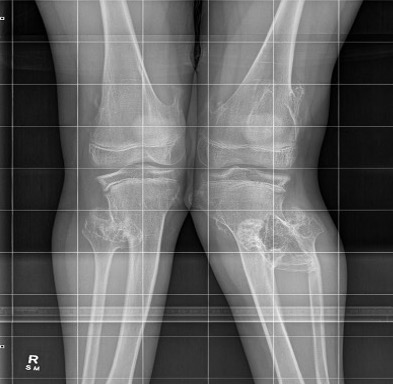

Knee - genu valgum

Genu Valgum OCMultiiple OCMultiple OC

Knee

Knee valgus OCOsteochondroma Knee Lateral

Guided growth / temporary hemi-epiphysiodesis

Osteotomy

Guided growth

Guided growth valgus HMEGuided growth 2 HME

Kang et al J Paediatr Orthop 2017

- 15 cases of MHE with genu valgum

- treated with hemi-epiphyseal stapling

- 67% satisfactory corrections

- correction slower than idiopathic valgus correction (1.5 years v 1 year)

Osteochondromas Valgus KneeOsteochondromas Knee Osteotomy 2Osteochondromas Knee Osteotomy AP